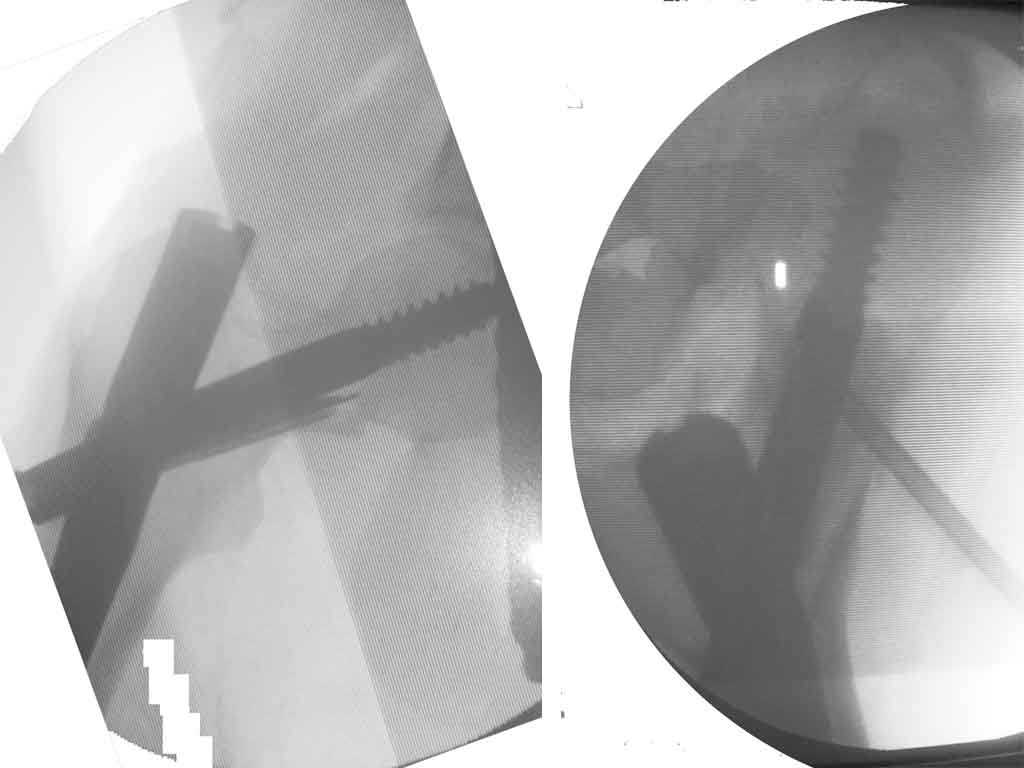

Приношу извинения, думал, что на прилагающейся рентгенограмме видно, что перелом произошел на месте обширной кисты, занимающей шейку и вертельную область. По характеру перелом многооскольчатый, дуга Адамса также представлена в виде осколков.

Приносим извинения за молчание. Больная прооперирована: под контролем ЭОП (защита плода несколькими халатами) выполнена закрытая репозиция на ортопедическом столе и фиксация Stryker Gamma 3 nail. Послеоперационные рентгенограммы мы решили не делать, чтобы не давать и без того чрезмерную нагрузку на плод. Поэтому придется довольствоваться картинкой с ЭОПа, правда сделанную на неподходящий для таких условий съемки фотоаппарат.

Да, забыли добавить, что во время оперции взят материал на гистологическое исследование (результат еще не получен) и в полость инъецирован жидкий OSTEOSET® (видно на аксиальной проекции). Металлокнструкции, которые видны на рентгенограммах - это те проводники, по которым вводился в полость OSTEOSET®.